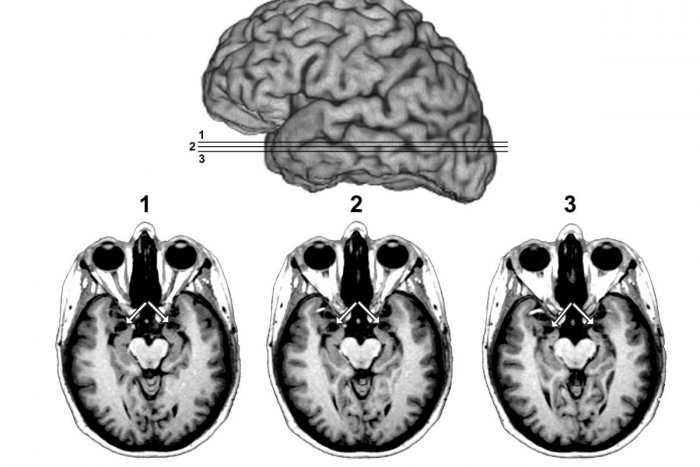

Ilustračný obrázok k článku Strašiak menom mozgová príhoda ohrozuje aj mladých Slovákov: TOTO sú príznaky